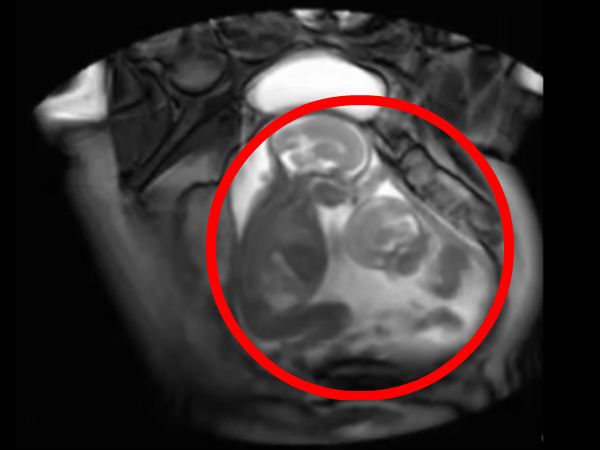

இரட்டையர்கள் பார்ப்பது என்றாலே ஆச்சரியமும், வியப்பும் தான். அதுவே அவர்கள் கருவில் அடித்து விளையாடுவதை பார்ப்பது என்றால்? இந்த காணொளிப்பதிவில் பாருங்கள்.

தாயின் கருவறையில் இருக்கும் இரட்டை சுசுக்கள், கருவில் வளரும் போதே ஒருவரை ஒருவர் அடித்து உதைத்து விளையாடி கொண்டிருப்பது போன்று காட்சிகள் கொண்டிருக்கிறது இந்த காணொளிப்பதிவு.

இந்த வீடியோ ஸ்கேனிங் செய்த பொது பதிவு செய்தது போன்று இருக்கிறது.

இந்த காணொளிப்பதிவில் இரட்டையர்கள் இருவர் அடித்து விளையாடுவது. ஒருவரை ஒருவர் மாறி, மாறி அடிக்க முயல்வது மிக தத்ரூபமாக இருக்கிறது. பிறந்த பிறகு அல்ல, கருவறையிலேயே நாங்கள் எங்கள் சுட்டித்தனத்தை துவங்கிவிட்டோம் என கூறுவது போல இருக்கிறது இந்த காணொளி.

இந்த காணொளிப்பதிவு உண்மையாகவே ஸ்கேனிங்கின் போது பதிவு செய்யப்பட்டதா? அல்ல கிராபிக்ஸ் உதவியால் உருவாக்கப்பட்டதா? என்ற கேள்விகள் மனதில் எழுந்தாலும். கருவில் வளரும் இரட்டையர்கள் ஒருவருடன் ஒருவர் விளையாடுவது உண்மையே என்கிறது அறிவியல்.